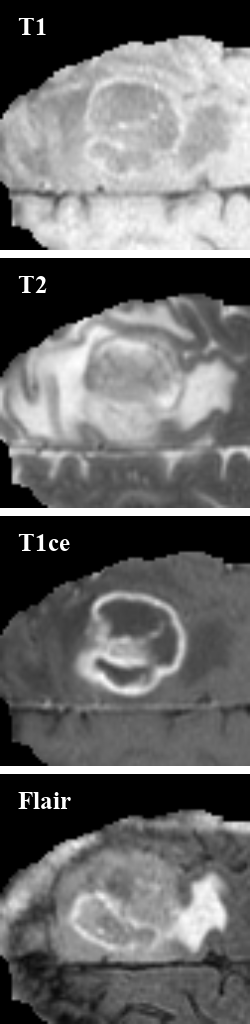

Brain tumors pose severe risks to human life, making precise medical segmentation essential as it devises effective treatment planning and strategies [1]. Brain tumor segmentation methods usually employ Multiple Magnetic Resonance Imaging (MRI) visualizations, including Fluid Attenuation Inversion Recovery (Flair), contrast-enhanced T1-weighted (T1ce), T1-weighted (T1), and T2-weighted (T2), as illustrated in Figure 1, as multiple modalities [2]. Particularly, the aforementioned modalities complement each other to understand both the physical structure and physiopathology of tumors; their combination naturally leads to improved segmentation performance [3, 4, 5, 6]. For instance, T2 and Flair imaging modalities are valuable for assessing the enhanced tumor (ET), whereas T1 and T1ce modalities are effective in delineating the core of the tumor, including the necrotic, non-enhancing, and enhancing regions (NCR/NET) [7]. However, not all modalities are always available in real clinical practice due to scenarios such as data corruption and/or variations in scanning protocols, leading to crucial challenges of developing a generalized multi-modal approach that copes with the absence of certain modalities [8, 9, 10, 11].

Refer to caption

Figure 1: Images of the four modalities in the brain tumor dataset with the ground truth (GT) segmentation label. Different colors represent different organs: Orange: NCR/NET, Yellow: ED, and Blue: ET.